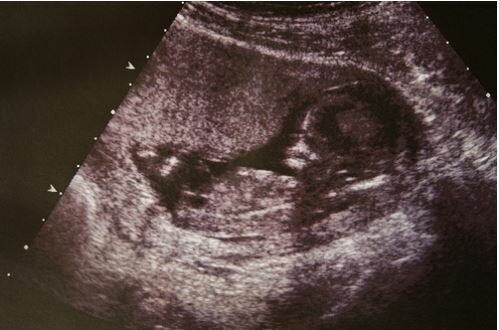

„Przez dziesięć miesięcy moja żona Brooklyn nosiła bardzo chore dziecko. Lekarze powiedzieli nam, że ma hydrocefalię. Ta choroba jest również nazywana wodogłowiem. Zwróciliśmy się do różnych lekarzy, do najlepszych specjalistów, których mogliśmy znaleźć, a oni jednogłośnie stwierdzili, że stan naszego dziecka był bardzo poważny”.

W pewnym momencie powiedziano nam, że wszystko jest na tyle złe, że po prostu nie ma sensu monitorować poziomu płynu w mózgu dziecka – lepiej już nie będzie. Prawie płakaliśmy, patrząc na wyniki tomografii. W pewnym momencie lekarze powiedzieli, że z prawdopodobieństwem 90 procent naszego chłopca umrze natychmiast po urodzeniu, a jeśli przeżyje, przerażającym jest nawet wyobrażenie sobie, jakie życie go czeka. Spotkaliśmy się z ekspertami, którzy wyjaśnili nam, jak wspierać życie naszego dziecka. Przeszliśmy straszny wykład, że w pewnym momencie możemy przestać zapewniać to wsparcie i pozwolić naszemu synowi „spocząć”.